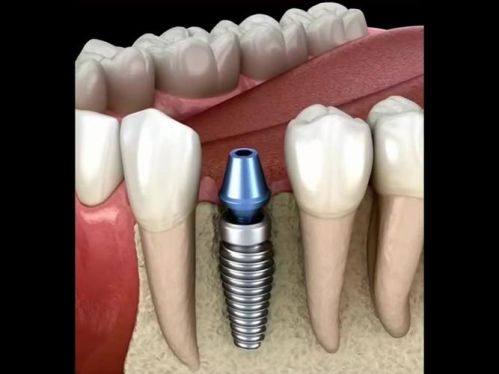

① 种植牙价格参考

| 项目 | 价格 |

|---|---|

| 韩国登腾种植牙 | 3500元起/颗 |

| 美国杰美 Zimmer | 4800元起/颗 |

| 瑞士 ITI 种植体 | 5800元起/颗 |

| 半口种植(韩系全固定) | 2.8万元起 |

| 全口种植(瑞士全固定) | 4万元起 |

| All-on-4 半口 | 5万元起 |

| All-on-6 全口 | 11万元起 |